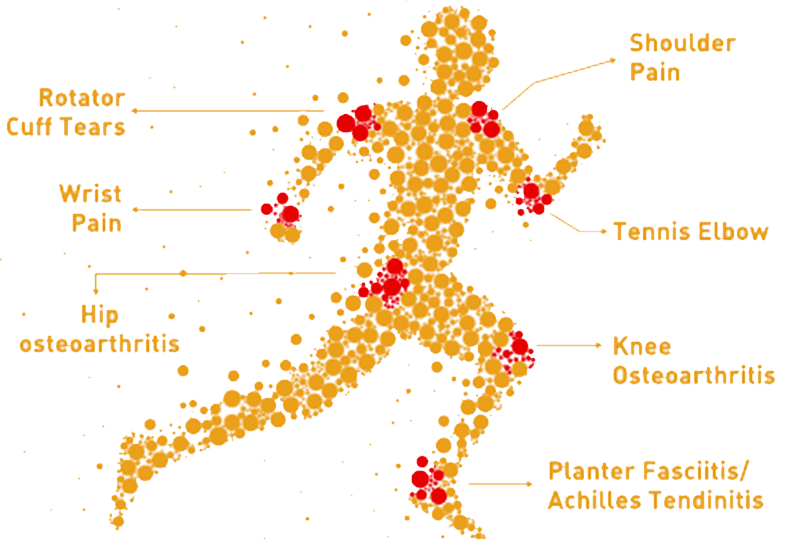

- Hip and Ankle Osteoarthritis

- Chronic Tendonitis/ Tendonitis in elbow, hip, knee, foot and ankle

- Tennis Elbow

- Plantar Fasciitis

- Acute ligament and muscle injuries in athletes